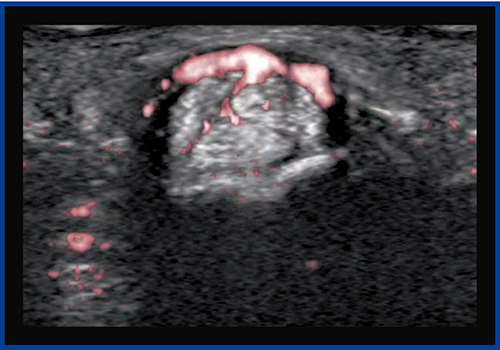

症例2は,Bモードにて中足骨と基節骨の関節の腫れと,関節液の貯留が確認され,一部に初期の骨びらんが疑われた(図5)。カラードプラ(図6)では,滑膜には豊富な血流が見られるが,骨びらんが疑われる部位にはほとんど血流が認められなかった。一方,SMI(図7)では,骨びらんの周囲から骨の中に流入する血流がわずかに認められた。

本症例は,未確定ではあるがリウマチが疑われる。通常,リウマチの診断はカラードプラを用いて行われるが,カラードプラでは滑膜の血流状態だけを見ているため,SMIを加えることで,リウマチ発生初期から見られる骨びらんを早期に評価できるようになると期待される。

図7 症例2のSMI画像

骨びらん周囲から骨の中に流入する血流をわずかに認める。